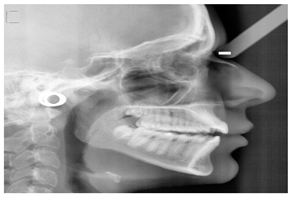

| Cephalometric projections | [65,94,95,96] | Orthodontic treatment planning. It captures a single film’s anterior, posterior, and lateral image of the skull bones and soft tissues. | ![]() | Typically collected from individuals who need orthodontic or orthognathic surgery. |